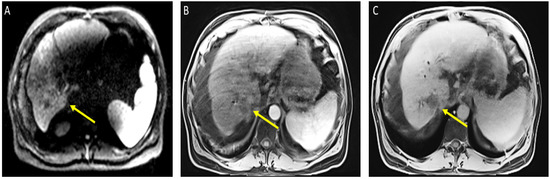

He was admitted for tumor evaluation which revealed a poorly differentiated, multifocal, grade 3 HCC. The Liver Imaging Reporting and Data System (LI-RADS) score was 5 (for arterial enhancement, washout, and size greater than 20 mm). Mild intrahepatic biliary dilatation secondary to mass effect was also noted. The tumor was confined to the liver with clear margins, no vascular invasion, normal regional lymph nodes by imaging criteria, and no evidence of distant metastasis, as can be seen in Figure 1.

Figure 1.

Magnetic resonance imaging of the abdomen. Limited by motion. Cirrhosis and splenomegaly were noted. Infiltrative segment 7 mass measures 6.5 × 4 cm. (A) Diffusion-weighted imaging (DWI) shows diffusion restriction of mass; (B) T1 with contrast shows vague arterial phase enhancement; (C) T1 post-contrast delayed phase imaging shows washout (captured at the diagnosis visit, and before the atezolizumab plus bevacizumab started).